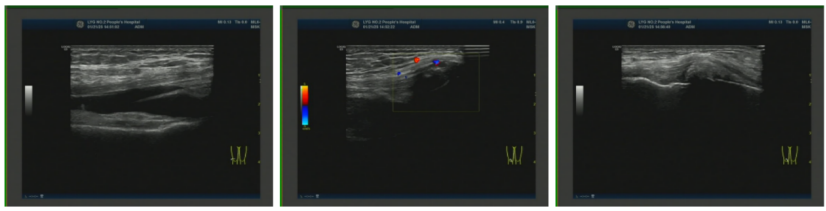

图4. 左侧腕关节浅表超声2025-01-21 右膝关节浅表超声:右侧膝关节积液;右侧膝关节滑膜炎伴痛风石形成,可见骨侵蚀;右侧股四头肌腱内强回声(痛风石?);右小腿软组织水肿(图5)。

图5.右膝关节浅表超声2025-08-16 第一跖趾关节浅表超声:双侧第一跖趾关节滑膜增厚伴痛风结晶形成(静止期)(图6)。